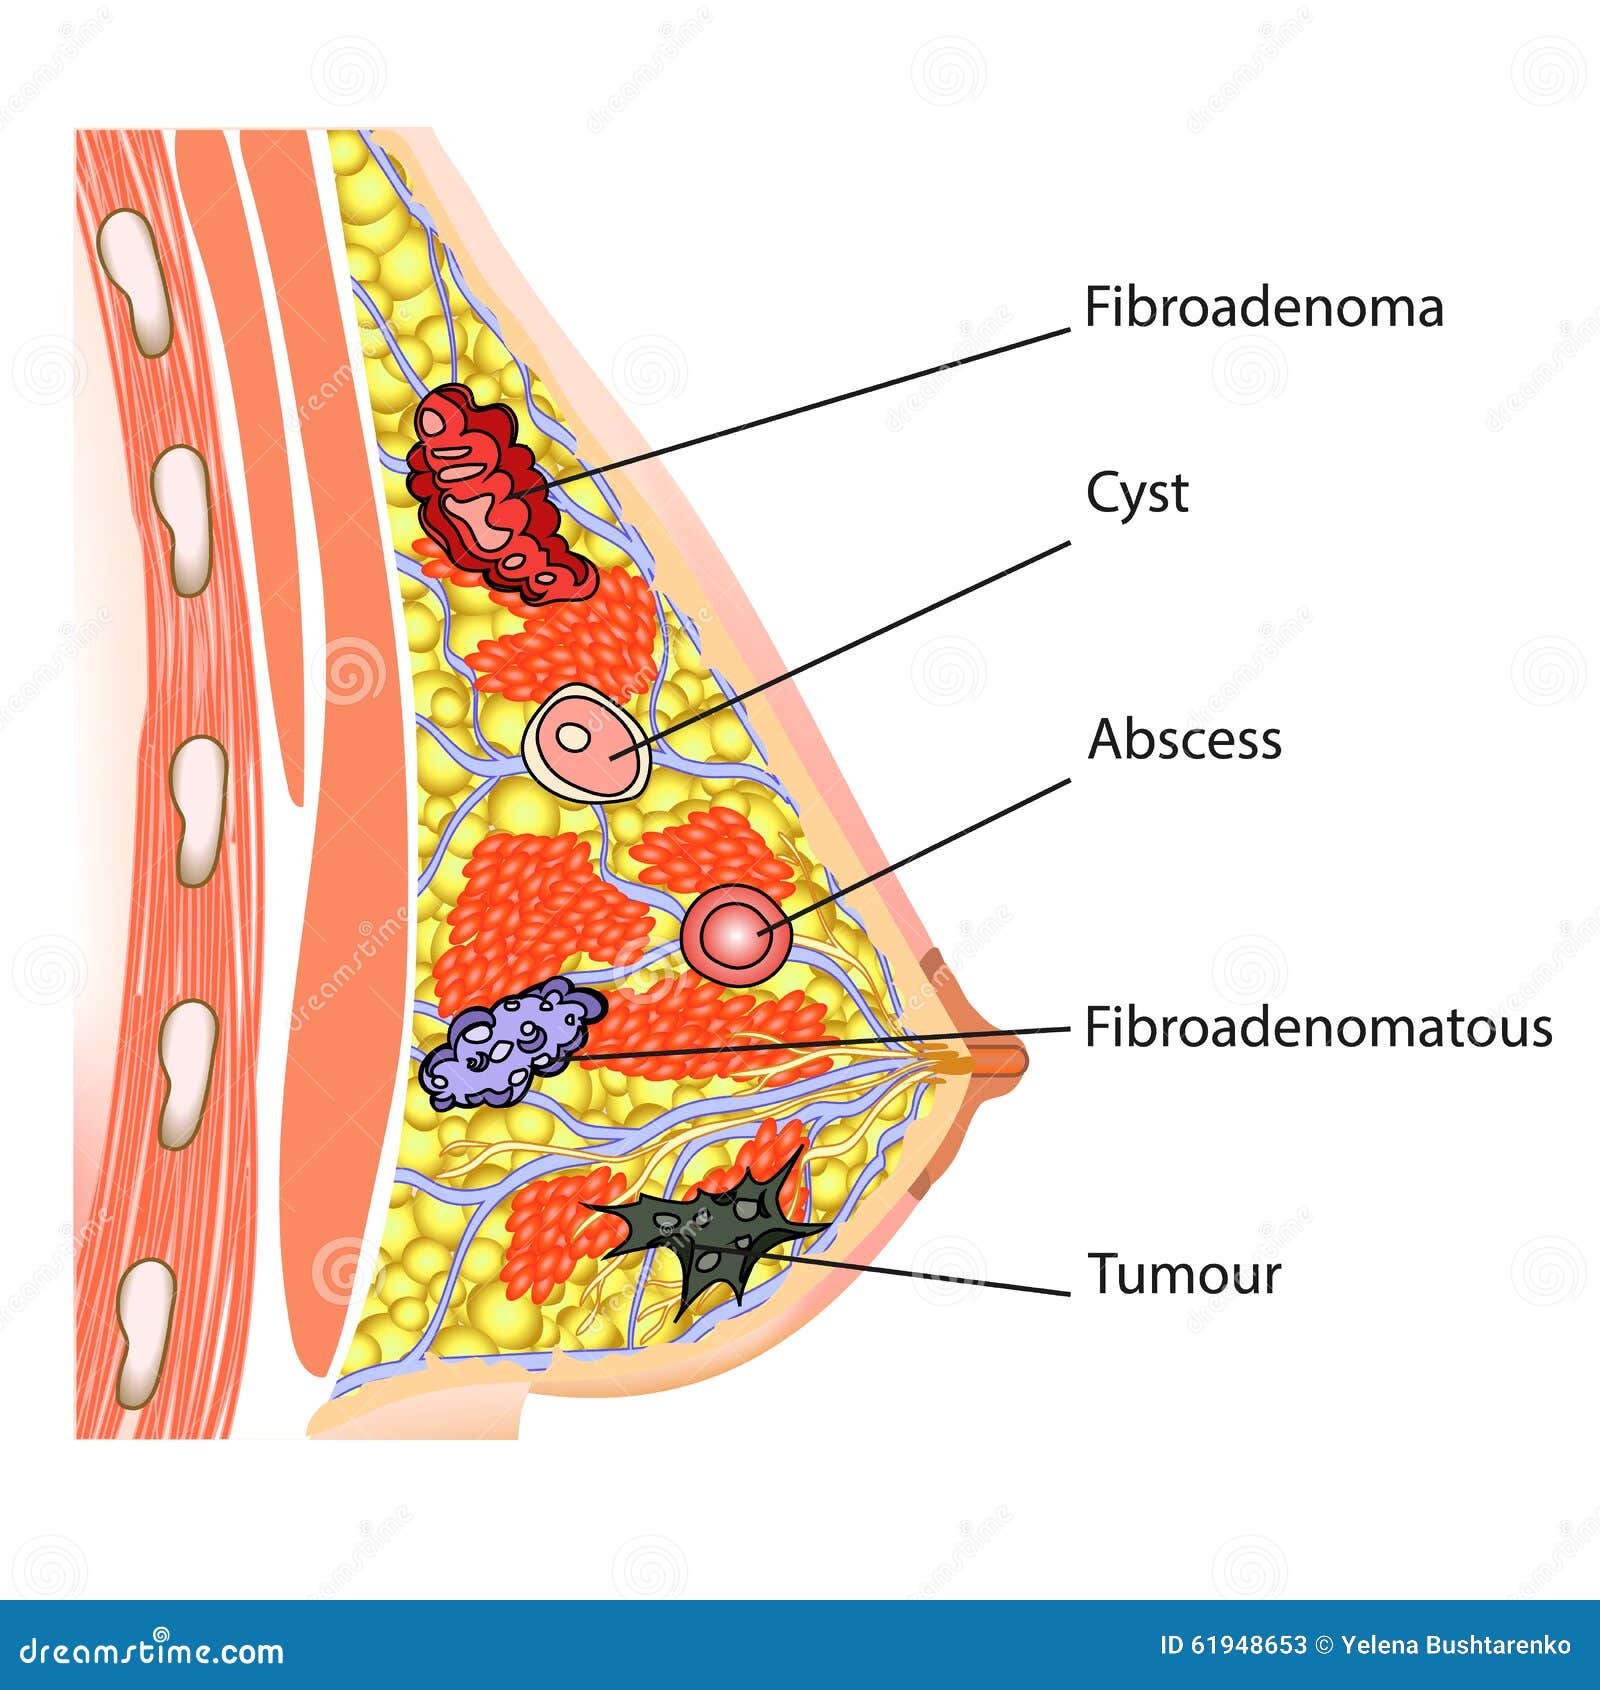

Уплотнения в груди могут быть вызваны различными причинами, включая кисты, фиброаденомы или инфекционные процессы. Важно понимать, как правильно подходить к их лечению и когда обращаться к врачу. Следующие советы помогут вам разобраться в этом вопросе и обеспечить здоровье своей груди.